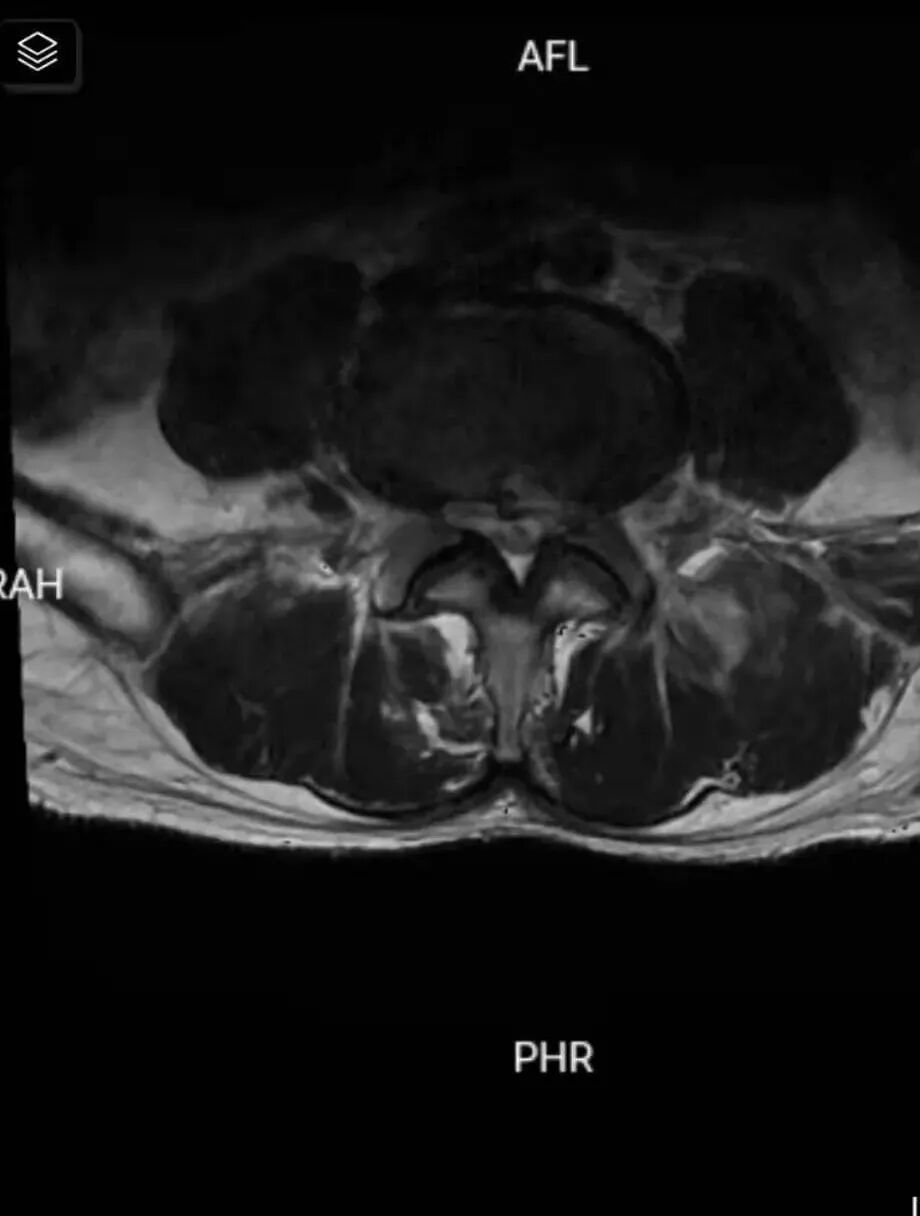

腰椎MRI检查结果提示为腰4/5椎间盘突出压迫神经,临床诊断为腰4/5椎间盘突出症。金博士在与患者沟通时表示:腰椎间盘突出症是较为常见的疾患之一,主要是因为腰椎间盘各部分(髓核、纤维环及软骨板),尤其是髓核,有不同程度的退行性改变后,在外力因素的作用下,椎间盘的纤维环破裂,髓核组织从破裂之处突出(或脱出)于后方椎管内,导致相邻脊神经根遭受刺激或压迫,从而产生腰部疼痛,一侧下肢或双下肢麻木、疼痛等一系列临床症状。而于先生突出的腰间盘碎片很小,这种小的椎间盘突出就好像一个人光着脚走路踩到大的石头不一定会很疼痛,但是踩到又小又尖的小石块会很疼痛一样,所以这种类型椎间盘突出患者往往疼痛感会更加强烈。

红色线条处是碎块很小的突出的间盘